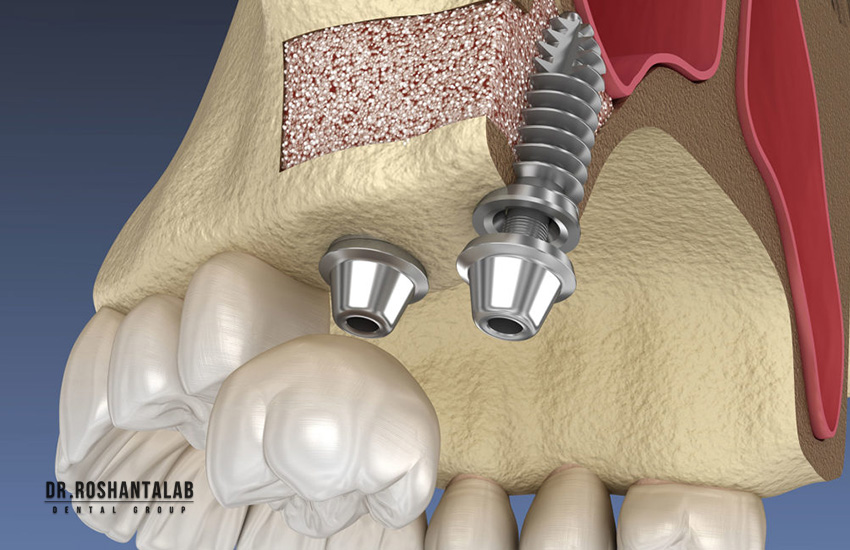

۱. نیاز به پیوند استخوان (Bone Grafting)

ایمپلنت دندان شبیه به پیچی است که باید در دیوار (استخوان) محکم شود. اگر استخوان فک شما در اثر کشیدن دندان در سالهای گذشته، عفونت، یا استفاده طولانیمدت از دندان مصنوعی تحلیل رفته باشد، قطر و ارتفاع کافی برای دربرگرفتن ایمپلنت را نخواهد داشت. در این حالت جراح مجبور است از پودر استخوان (آلوگرافت، زنوگرافت یا استخوان خود بیمار) برای بازسازی فک استفاده کند.

اگر تحلیل جزئی باشد، پیوند همزمان با کاشت ایمپلنت انجام میشود که زمان را خیلی طولانی نمیکند. اما اگر تحلیل شدید باشد (مثلاً عرض استخوان کمتر از ۳ میلیمتر باشد)، ابتدا باید عمل بازسازی استخوان (Ridge Augmentation) انجام شود، ۴ تا ۶ ماه زمان داده شود تا پودر استخوان تبدیل به استخوان زنده شود، و سپس ایمپلنت کاشته شود. این کار پروسه درمان را دو برابر میکند.

۲. جراحی سینوس لیفت (Sinus Lift)

در فک بالا، در ناحیه دندانهای آسیاب (خلفی)، حفرههای هوایی بزرگی به نام سینوسهای ماگزیلاری وجود دارند. وقتی دندانهای آسیاب بالا کشیده میشوند، استخوان زیر سینوس به سرعت تحلیل رفته و کف سینوس به سمت پایین (سمت دهان) افتادگی پیدا میکند. در نتیجه، استخوان کافی برای ایمپلنت باقی نمیماند و اگر جراح ایمپلنت را بکارد، نوک ایمپلنت وارد فضای سینوس شده و باعث عفونت سینوزیت میشود. در این شرایط، جراحی “سینوس لیفت” (بالا بردن کف سینوس) انجام میشود. غشای سینوس با احتیاط به بالا رانده شده و زیر آن پودر استخوان ریخته میشود. سینوس لیفت باز (Open Sinus Lift) معمولاً نیازمند ۶ ماه زمان بهبودی پیش از کاشت یا قرار دادن روکش است.